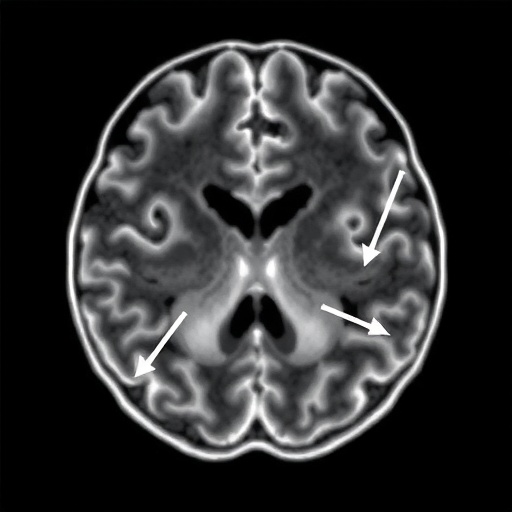

The human brain is a marvel of biological engineering, a labyrinth of neurons fueled by a relentless demand for oxygenated blood, yet for those living with the enigmatic condition known as Moyamoya arteriopathy, this vital supply line is under constant siege. Derived from the Japanese word for a puff of smoke, Moyamoya describes the hazy appearance of fragile collateral vessels that sprout in a desperate attempt to bypass the progressive narrowing of the internal carotid arteries. While the medical community has long understood the structural decay associated with this disease, particularly in pediatric populations, the ability to predict when a catastrophic stroke might occur has remained frustratingly elusive. However, a groundbreaking longitudinal study published in the prestigious journal Pediatric Research has unveiled a predictive frontier that could fundamentally alter how we monitor at-risk patients, shifting the paradigm from reactive management to proactive prevention through the sophisticated use of Transcranial Doppler ultrasound.

Diving deeper into the technicalities of the study, the researchers observed that it isn’t just the absolute speed of blood but the asymmetry of velocities across the brain’s hemispheres that provides the most definitive clues. In many cases of Moyamoya, the disease progresses unevenly, creating a hemodynamic imbalance that further stresses the fragile “puff of smoke” vessels. The study’s data indicates that when one side of the brain shows a dramatic spike in velocity compared to the other, the risk of a localized stroke or “silent” infarct increases exponentially. This nuanced understanding of intracranial hemodynamics allows for a more personalized approach to medicine, where treatment plans are tailored to the specific flow patterns of an individual’s brain rather than a one-size-fits-all protocol based on general age or symptom presentation.